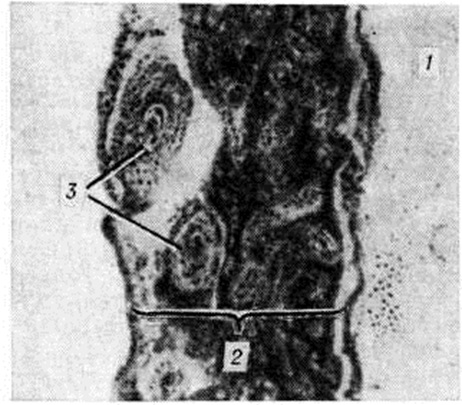

При гнойном Менингит воспалительный выпот имеет сначала серозный характер, а на 2—3-й день заболевания он приобретает вид гнойного экссудата. При этом мягкие оболочки полушарий мозга (цветной рисунок 1), сосудистые сплетения и эпендима пропитаны мутной желтовато-зеленоватой вязкой ЖИДКОСТЬЮ. При обильном накоплении гнойнофибринозный экссудат образует «чепчик» в лобной и теменной долях полушарий (цветной таблица, ст. 33, рисунок 2) или окутывает весь мозг сплошной массой. Он заполняет также мозговые полости, покрывая желтоватой плёнкой сплетения и стенки желудочков. Развивающаяся обтурация ликворных путей выпотом ведёт к острому расширению желудочков мозга (цветной рисунок 3) и церебральной гипертензии. В воспалительный процесс могут вовлекаться подоболочечные отделы мозгового вещества, но особенно часто области, окружающие желудочки. При своевременно начатом лечении гнойный экссудат подвергается ферментативному распаду и резорбции, но в некоторых случаях он организуется, вызывая спаечный процесс в оболочках и желудочках мозга. Развивается хронический гнойный или хронический продуктивный (адгезивный) лептоменингит, характеризующийся частичной облитерацией подпаутинного пространства с образованием между листками мягкой оболочки замкнутых гнойных или серозных полостей. Спайки могут рассекать также и желудочки мозга, формируя отдельные заполненные гноем или цереброспинальной жидкостью камеры. Макроскопическую картину хронический продуктивного Менингит дополняет склероз оболочек, сплетений и эпендимы с полной или частичной облитерацией находящихся здесь сосудов. Резко нарушаются циркуляция цереброспинальной жидкости и мозговая гемодинамика, что ведёт к развитию гидроцефалии. Гистологически в оболочках, эпендиме и сплетениях обнаруживается картина хронический гнойного воспаления с выраженными склеротическими изменениями. В соседних участках мозговой ткани можно наблюдать поля клеточного опустошения с дистрофией и гибелью нейронов и накоплением в них липофусцина, демиелинизацию нервных волокон и очаговый глиоз. Описанные изменения могут выявляться и без предшествующей клиники острого Менингит, через несколько лет после травмы, инфекционного заболевания или оперативного вмешательства. Если в оболочечном выпоте содержатся эритроциты и, следовательно, мягкие мозговые оболочки окрашиваются в различные оттенки красного цвета, то такое воспаление этих оболочек носит название геморрагического (цветной рисунок 2). Геморрагический лептоменингит (цветной рисунок 4) может осложнить инфекционные заболевание, сопровождающееся общим тромбогеморрагическим синдромом или местной гиперергической реакцией немедленного типа. Сходную макроскопическую картину из-за примеси крови имеет реактивное воспаление в зоне субарахноидального кровоизлияния. Дифференциальной диагностике в этих случаях может помочь гистологический исследование материала — при инфекционном геморрагическом Менингит обнаруживают фибриноидные некрозы сосудов (смотри полный свод знаний Фибриноидное превращение), их тромбоз и преимущественно гранулоцитарную инфильтрацию очага воспаления. Туберкулёзный лептоменингит — результат гематогенной генерализации или лимфогенного распространения инфекции из лёгочного, лимфожелезистого (или другого внелёгочного) очага. Современные методы лечения изменили морфологический картину заболевания. На смену острому серозно-фибринозному воспалению оболочек мозга, дававшему раньше почти 100% летальность, пришли хронический ограниченные формы поражения со значительно лучшим прогнозом. При остром туберкулёзном Менингит желатинозный серовато-желтоватый выпот обнаруживается в подпаутинном пространстве головного (цветной рисунок 5) и спинного мозга в типичных местах, а также в полостях мозга. В мягкой оболочке и в эпендиме заметны милиарные или более крупные сероватые бугорки (цветной рисунок 6). Пропитанная серозно-фибринозным выпотом ткань может подвергаться казеозному некрозу (цветной рисунок 7). Микроскопически в инфильтрате с первых же дней заболевания преобладают лимфоциты. Самой характерной гистологический чертой подострых и хронический форм туберкулёзного воспаления является образование преимущественно эпителиоидно-клеточных гранулем (цветной рисунок 5), нередко с казеозным некрозом их центра. Подобные гранулемы обнаруживаются и в стенке сосудов, в которых можно видеть также и другие изменения — от серозного пропитывания до фибриноидного и казеозного некроза с тромбозом и развитием инфарктов головного мозга. При туберкулёзном Менингит в воспалительный процесс часто вовлекаются смежные отделы мозговой ткани, в которой развивается картина казеозного (цветной рисунок 6) или гранулематозного (рисунок 2) энцефалита. В исходе туберкулёзного воспаления в субарахноидальном (и даже субдуральной) пространстве головного и спинного мозга могут возникать спайки. Просвет проходящих здесь сосудов облитерируется (рисунок 3 и 4), что приводит к тяжёлым нарушениям циркуляции цереброспинальной жидкости и к расстройству гемодинамики. При амёбном Менингит (менингоэнцефалите), вызываемом неглериями, патолого-анатомически выявляется гнойный лептоменингит, геморрагический некротизирующий менингоэнцефалит, отёк мозга, периваскулярные скопления амёб. Морфологически картина при менингоэнцефалите акантамебного происхождения проявляется гранулематозным энцефалитом с очаговыми некрозами. Клиническая картинаМенингеальный синдром и изменения цереброспинальной жидкостиДля всех форм Менингит характерно наличие симптомов, объединяемых в менингеальный, или оболочечный, синдром. Полный менингеальный симптомокомплекс наблюдается не всегда даже при гнойном Менингит Нередко, особенно у детей раннего возраста, лиц старческого возраста, выявляется лишь часть менингеальных симптомов. К менингеальному синдрому относятся головная боль, рвота, общая гиперестезия, специфическая менингеальная поза, ригидность затылочных мышц, симптомы Кернига, Брудзинского, симптом подвешивания Лесажа, скуловой симптом Бехтерева н другие Головная боль — постоянный симптом, наблюдается практически у всех больных при различных формах Менингит Она может быть диффузной или локализованной (преимущественно в области лба и затылка). Возникновение головной боли связано с раздражением чувствительных окончаний тройничного нерва, а также парасимпатических (блуждающий нерв) и симпатических волокон, иннервирующих оболочки головного мозга. Рвота обычно сопровождает головную боль, возникает без связи с приёмом пищи, имеет «фонтановидный» характер. Рвота при Менингит— центрального происхождения и связана с раздражением рецепторов блуждающего нерва пли его ядер, расположенных на дне IV желудочка, или рвотного центра в ретикулярной формации продолговатого мозга. Важным симптомом является общая кожная гиперестезия и повышенная чувствительность к звуковым и световым раздражителям (гиперакузия, светобоязнь). Выявление этого симптома в раннем детском возрасте затруднено, так как дети обычно негативно относятся к осмотру, раздражаются при прикосновении к ним, капризничают, отворачиваются при ярком свете. В основе общей гиперестезии лежит раздражение задних корешков, а возможно и клеток спинномозговых узлов. Характерна поза больного: запрокинутая голова, выгнутое туловище, «ладьевидный» втянутый живот, руки прижаты к груди, ноги подтянуты к животу (менингеальная поза, поза «лягавой собаки», «взведённого курка»). Менингеальная поза — следствие рефлекторного тонического сокращения мышц. Запрокинутая голова больного обусловлена ригидностью затылочных мышц — повышением тонуса мышц-разгибателей шеи. При попытке наклонить вперёд голову больного, находящегося в положении лёжа, выявляется напряжение мышц затылка, при этом подбородок больного привести к грудной клетке не удаётся. Любая попытка вывести голову больного из её фиксированного положения сопровождается резкой болезненностью. Симптом Кернига (смотри полный свод знаний Кернига симптом) — очень ранний и характерный симптом поражения мозговых оболочек. Он выражается в невозможности разогнуть в коленном суставе ногу, предварительно согнутую под прямым углом в коленном и тазобедренном суставах (рисунок 5). Следует отличать симптом Кернига от анталгического (мышечного) сопротивления при симптоме Ласега (смотри полный свод знаний Радикулит). У детей раннего возраста симптом Кернига может не выявляться. У новорожденных и детей первых двух месяцев жизни, а также у больных паркинсонизмом, миотонией симптом Кернига может быть следствием физиологический или патологический повышения общего тонуса мышц. Верхний симптом Брудзинского выражается в непроизвольном сгибании ног в коленных суставах в ответ на попытку привести голову к груди в положении лёжа на спине (рисунок 6). Скуловой симптом Брудзинского — та же реакция при перкуссии скуловой дуги. Лобковый симптом Брудзинского выражается в сгибании ног в коленных суставах при надавливании на лонное сочленение. Нижний симптом Брудзинского исследуется одновременно с симптомом Кернига: при попытке разогнуть ногу в коленном суставе вторая нога сгибается в колене и приводится к животу. Симптом Гийена аналогичен нижнему симптому Брудзинского — при сдавливании четырех-главой мышцы одной ноги другая нога сгибается в колене и приводится к животу. Напряжение длинных мышц спины является также частым и типичным признаком менингеального синдрома и выявляется в виде следующих симптомов. Симптом Мейтуса: больному, лежащему на спине, фиксируют разогнутые в коленях ноги правой рукой, а левой рукой поддерживают спину, помогая ему сесть. При менингеальном синдроме спина больного и разогнутые ноги в положении сидя образуют тупой угол: больной не может сидеть прямо при разогнутых ногах. Симптом Фанкони — невозможность самостоятельно сесть в постели при разогнутых и фиксированных коленях. Симптом «треножника» — больной может сидеть в кровати, лишь опираясь руками позади спины. Симптом «поцелуя колена» — больной не в состоянии даже при согнутых в тазобедренных суставах нижних конечностях прикоснуться губами к колену. Довольно постоянным у больных всех возрастов является скуловой симптом Бехтерева: при перкуссии скуловой дуги усиливается головная боль и непроизвольно возникает болезненная гримаса на соответствующей половине лица. У детей раннего возраста определяется симптом подвешивания Лeсажа: поднятый под мышки ребёнок подтягивает ноги к животу и сохраняет их в этом положении, при этом голова слегка запрокинута назад (здоровый ребёнок при этой пробе свободно сгибает и разгибает ноги). Большое диагностическое значение у детей раннего возраста имеет симптом Флатау — расширение зрачков при быстром наклоне головы вперёд.